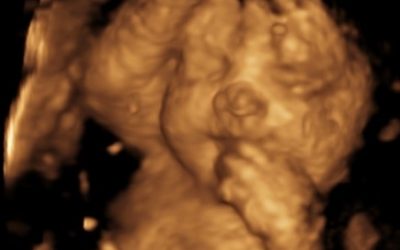

Early Pregnancy & Viability Scans • Gender Scans • Growth & Well-being Scans • 4D Scans